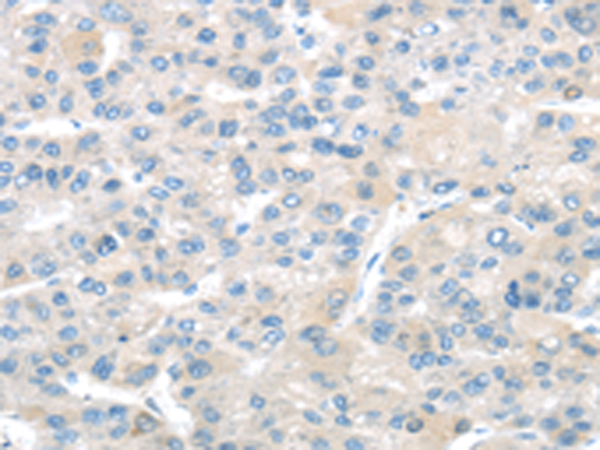

分类: 科研抗体货号: P08887别名: ECRG1应用: IHC反应种属: Human